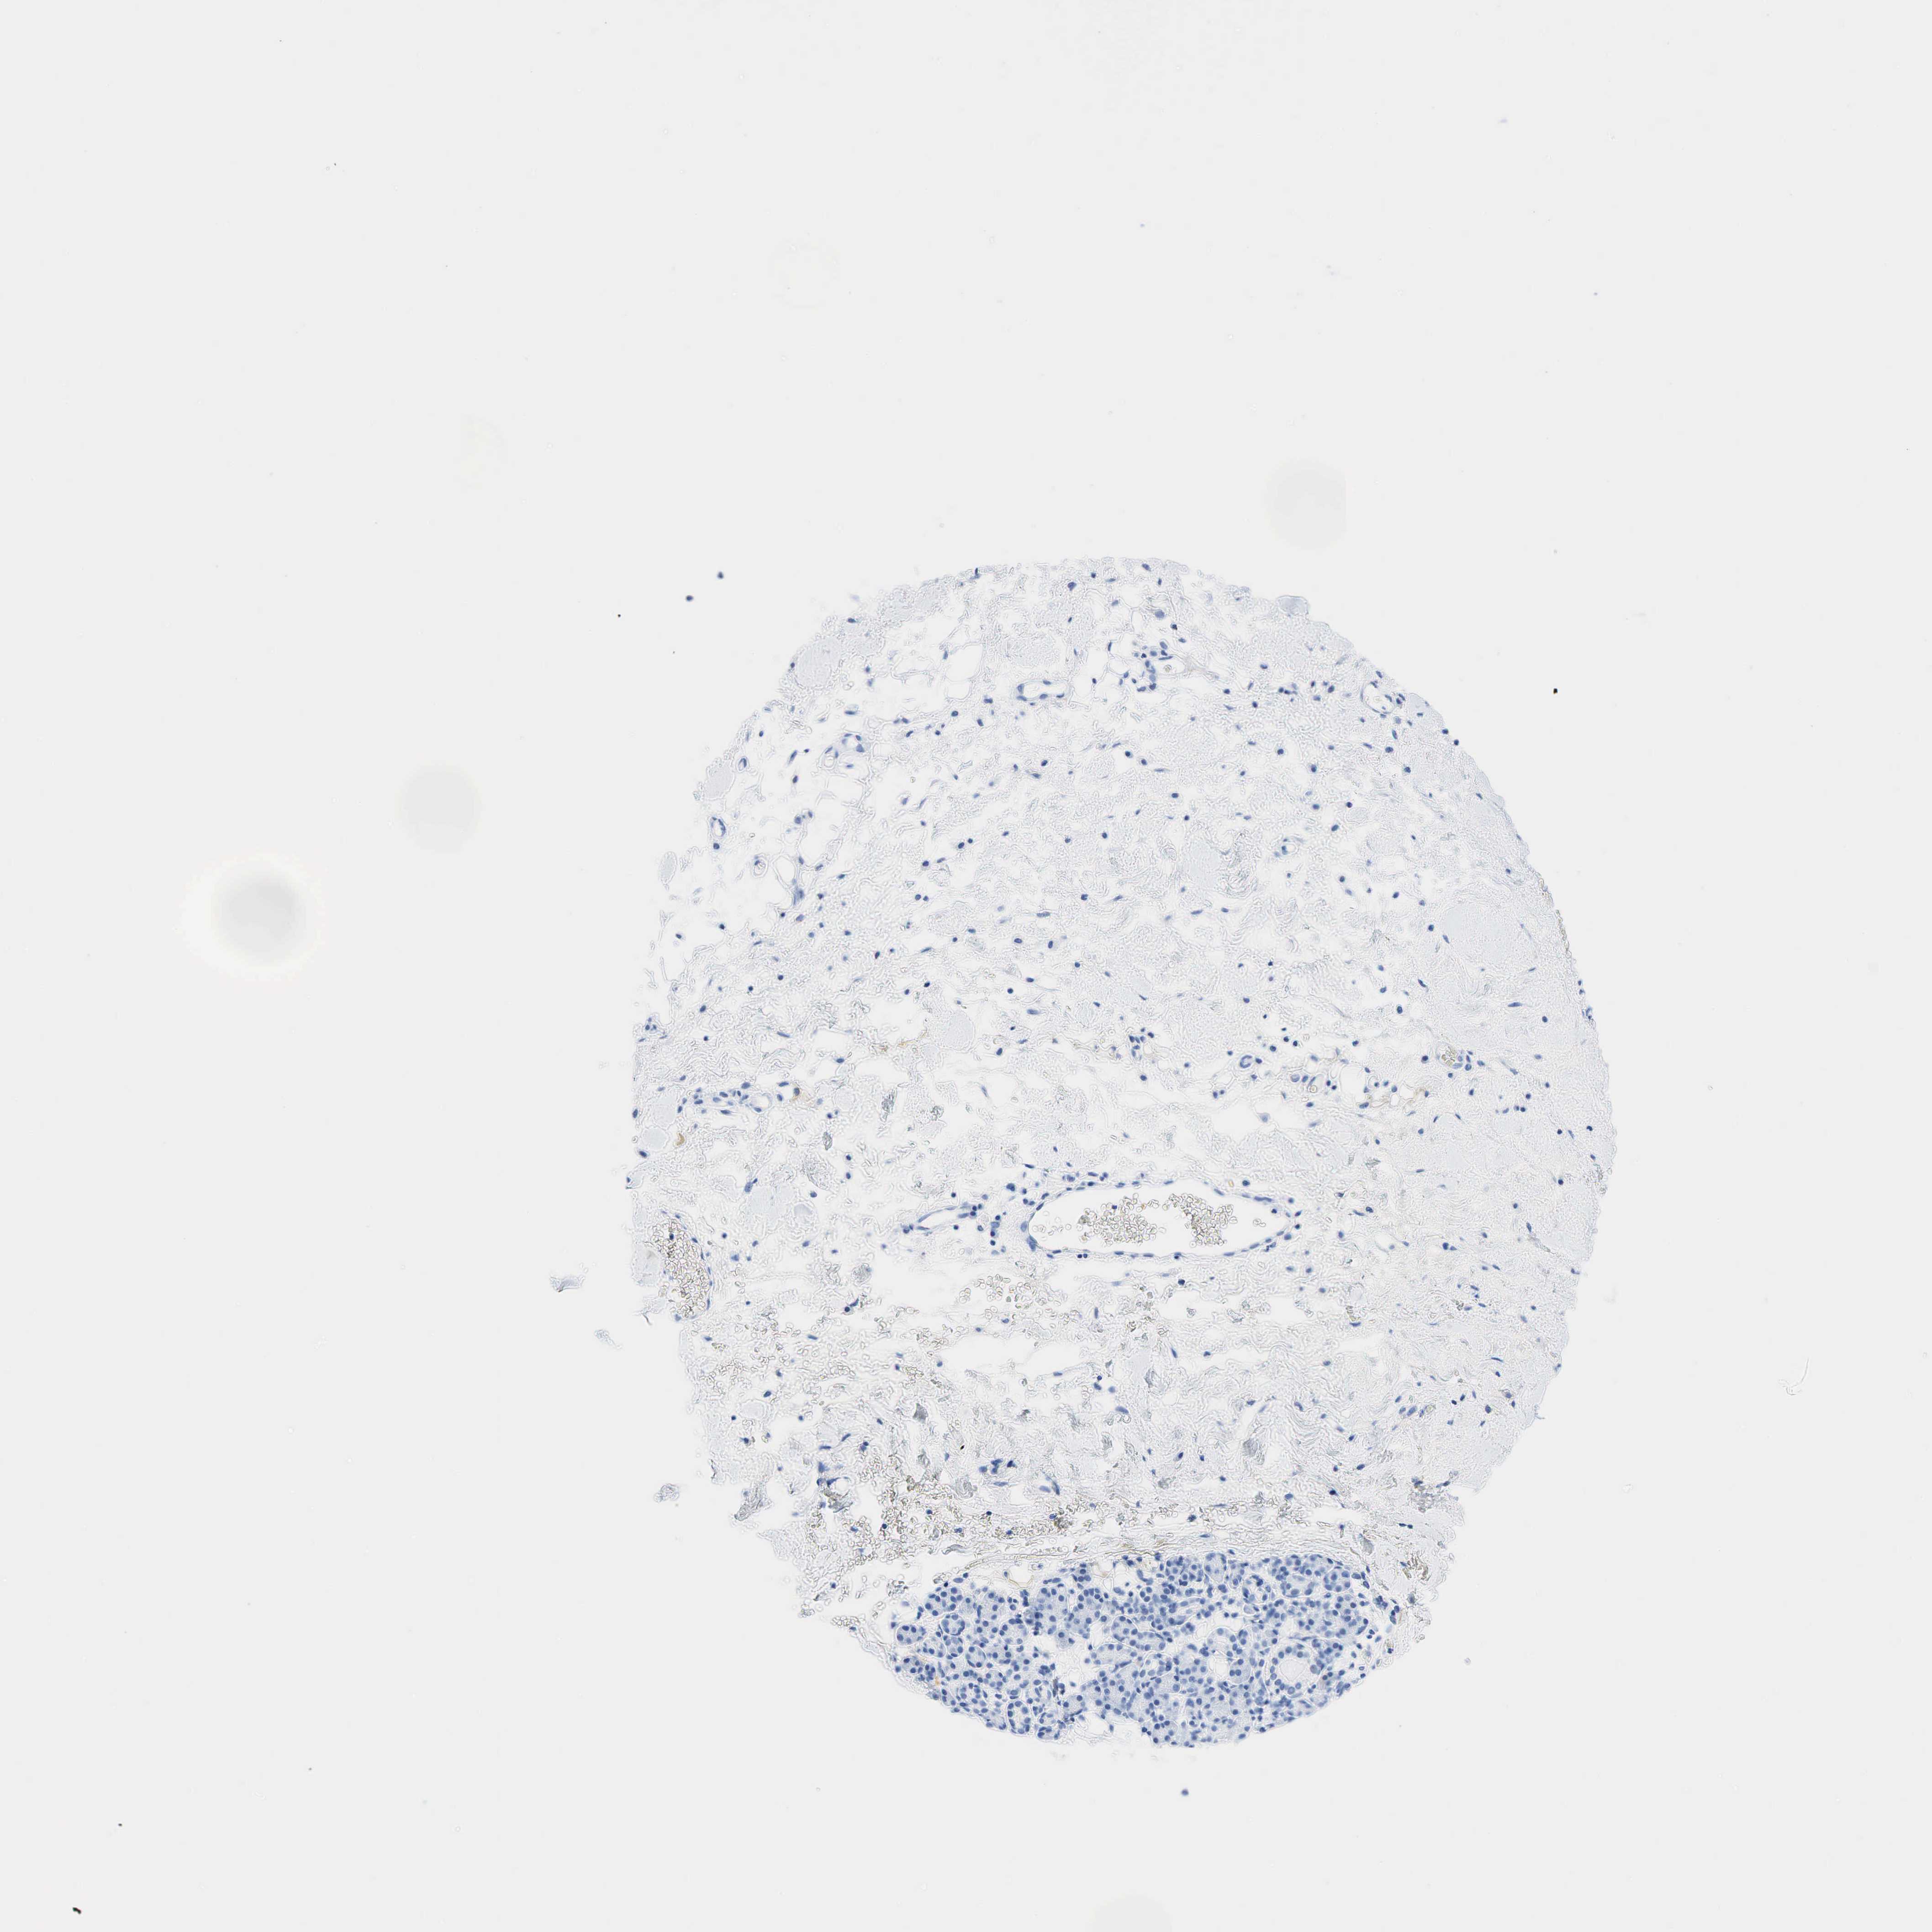

SKIN CANCER - Protein expressioni

A mouse-over function shows sample information and annotation data. Click on an image to view it in a full screen mode. Samples can be filtered based on level of antibody staining by selecting one or several of the following categories: high, medium, low and not detected. The assay and annotation is described here.

Antibody stainingi

Antibody staining in the annotated cell types in the current human tissue is reported as not detected, low, medium, or high, based on conventional immunohistochemistry profiling in selected tissues. This score is based on the combination of the staining intensity and fraction of stained cells.

Each image is clickable and will lead to virtual microscopy that enables deeper exploration of all samples and also displays staining intensity scores, fraction scores and subcellular localization as well as patient and tissue information for each sample.

Squamous cell carcinoma, NOS

Squamous cell carcinoma, metastatic, NOS

Basal cell carcinoma